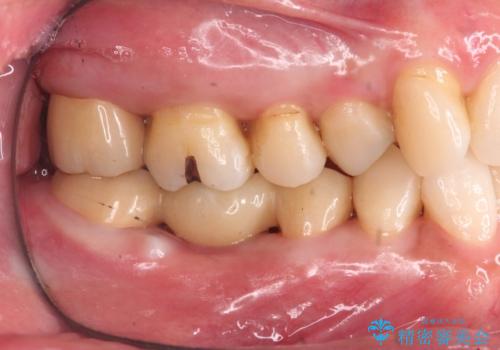

- 他院で虫歯治療に伴い初めての神経の治療を行ったところ、神経の治療自体10回以上通った上に抜歯と言われたとのことでした。

初診時には歯肉が腫れており、膿が出ている状態でした。

また、根の詰め物が根尖孔外(根の先の外の骨の部分)に盛大に漏れ出しており、歯周ポケットと根尖病巣が交通しているような状態でした。

初めての根の治療には見えないくらい、かなり歯が削ってあり、薄くなっていて割れても仕方ない状態でした。前の状態を見ていないので何とも言い難いですが、他の歯に比べこの歯だけ極端に状態が悪かったです。